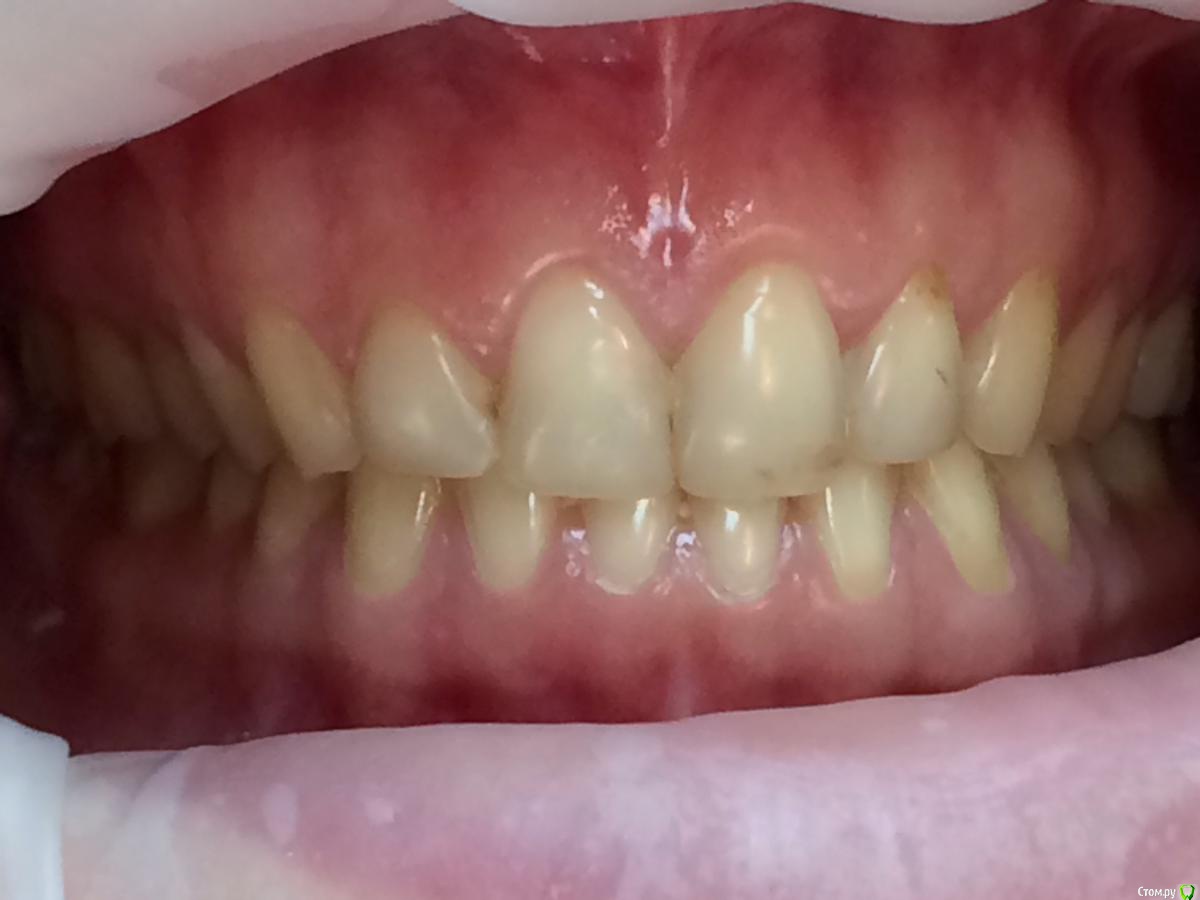

Larnary Опубликовано 28 июля, 2015 Поделиться Опубликовано 28 июля, 2015 (изменено) Добрый день!Ко мне обратилась пациент 1988 гр с жалобой на стираемость зубов и постоянные сколы пломб.Объективно небная поверхность верхних резцов стерта до дентина. Окклюзионная стираемость жевательной группы зубов.Прошу помочь с выявлением причины такой стираемости зубов и оптимальноно метода лечения Изменено 28 июля, 2015 пользователем Larnary Ссылка на комментарий

Larnary Опубликовано 28 июля, 2015 Автор Поделиться Опубликовано 28 июля, 2015 (изменено) Видно окклюзионнык интерференции в области 37 и 47.На днях удален 38 и дальше будут удалены остальные восьмерки. На ТРГ мне видится небольшая ретрузия верхних резцов,дистальный прикус. Так же левпя окклюзионная кривая более выраженная,чем правая Изменено 28 июля, 2015 пользователем Larnary 1 Ссылка на комментарий

Skip Опубликовано 29 июля, 2015 Поделиться Опубликовано 29 июля, 2015 На ТРГ мне видится небольшая ретрузия верхних резцов,дистальный прикус. Так же левпя окклюзионная кривая более выраженная,чем правая Доброе утро! Если отталкиваться от анализа ТРГ, то там нет выраженного дистального прикуса, хотя какие-то 0,2 мм. присутствуют, но это ерунда. Скелетное соотношение челюстей Класс I, но есть другая проблема, которая на скриншоте ниже обведена красным: http://i10.pixs.ru/storage/5/2/2/65456789jp_9935083_18202522.jpg Skeletal Deep bite или Скелетный глубокий прикус. Заметьте, не Зубной глубокий прикус, а именно Скелетный и это будет работать в Вашу пользу при планировании лечения. Если встречается комбинация глубокого Зубного и Скелетного, то эти случаи сложнее открыть. http://i11.pixs.ru/storage/5/3/1/0987645678_6395482_18202531.jpg В отношении верхних резцов, то всё правильно Вы отметили, они действительно в ретрузии (-4 мм.) и угол их инклинации уменьшен, как собственно и угол инклинации нижних резцов, а другими словами, мы имеем соотношение резцов 2-го подкласса. Это обстоятельство служит достаточно высоким риском развития внутрикапсулярных проблем ВНЧС. В вашем случае, интуиция мне как-то подсказывает, что там вероятно существует гипермобильность, но могу и ошибаться. Резцы 2-го подкласса могут объяснить и стриаемость этих зубов, учитывая, как Вы наверное знаете, дисгармонию между углом суставного пути и угла инклинации резцов Но вот ещё одно обстоятельство, на которое хотелось бы обратить внимание и которое нужно отметить в Вашем проблемном списке. Опять же, исходя из анализа ТРГ. Из этого анализа следует, что верхняя челюсть длинная и расположена в ретропозиции. Вы это никак уже не измените, но как при этом будет вести себя нижняя челюсть? Из собственной практики, я заметил, что нижняя челюсть, при этих обстоятельствах, частенько позиционируется кпереди в центральной окклюзии, обеспечивая, тем самым, нормализацию такой жизненно важной функции, как дыхание. И если Вы проведёте, к примеру, нейромышечную регистрацию физиологического положения нижней челюсти, а иными словами регистрацию прикуса, то вполне сможете обнаружить, что нижняя челюсть окажется в ретроположении. И получаем, в итоге, такой недоделанный природой Класс II, так ведь..? Это как раз то, когда повышая прикус, мы, впоследствии, сталкиваемся с проблемой т.н. двойного прикуса. Может нижняя челюсть и сметала всё мешающее ей на своём пути, когда постоянно стремилась находиться кпереди..? Кстати, при 2-ом классе нижняя челюсть практически всегда любит находится чуть кпереди, но это так, для кругозора... Есть ещё одно обстоятельство, которое может наносить сокрушительный удар по твёрдым структурам зубов. Оговорюсь сразу, что я не сторонник разных там теорий, так или иначе связанных с психикой, стрессом и так далее. В связи с этим у меня к Вам вопрос. Вы проводили монтаж моделей в артикуляторе с лицевой дугой или по средним значениям? Если с лицевой дугой, то хотелось бы взглянуть, как там модель верхней челюсти расположена в пространстве артикулятора. Нет ли там бокового смещения модели от центра верхней рамы..? То, что с левой стороны окклюзионная кривая глубже, то это носит адаптационной характер, связанный с левым суставом, поэтому нужно провести мониторинг ВНЧС, на предмет внутрикапсулярных расстройств этого сочленения (объём вертикальных и горизонтальных движений ROM). На ТРГ, кстати, можно заметить, как раздваивается нижний край тела нижней челюсти и это неспроста. 3 Ссылка на комментарий

Bobby Опубликовано 29 июля, 2015 Поделиться Опубликовано 29 июля, 2015 Фасетки стираемости на нёбных поверхностях верхних резцов и вестибулярных поверхностях нижних резцов обусловлены малым оверджетом - недостаточная щель по саггитали, поэтому и будут колоться реставрации, а ткани зубов истираться. Фрадеани про это на своём курсе рассказывал и показывал видео как это диагносцировать и что с этим делать. Что вообще хочет пациентка и на что готова? Эти вопросы лучше сразу решать на первичной консультации, а то делаете диагностики, всё рассчитываете, распинаетесь, а они потом: "ой, я пока не готов/а к такому плану лечения" и всё заканчивается композитной мазнёй в другой клинике. 5 Ссылка на комментарий

zzkz Опубликовано 29 июля, 2015 Поделиться Опубликовано 29 июля, 2015 Со слов Коиса понял, что в данном случае было бы достаточно создать достаточное функциональное пространство для резцов нижней челюсти, путем брекетов например, вывести передние резцы в/ч в протрузию Ссылка на комментарий

Bobby Опубликовано 29 июля, 2015 Поделиться Опубликовано 29 июля, 2015 Со слов Коиса понял, что в данном случае было бы достаточно создать достаточное функциональное пространство для резцов нижней челюсти, путем брекетов например, вывести передние резцы в/ч в протрузиюИменно! А иногда это пространство можно создать за счёт легкого изменения угла коронковой части зубов (за счёт керамических рестарваций - если к ним есть показания, а в данном случае они как раз есть). Ссылка на комментарий

Maverick Опубликовано 9 августа, 2015 Поделиться Опубликовано 9 августа, 2015 (изменено) Думаю в данном кейсе интрузия резцов будет нежелательна, десневые контуры фронтальной группы зубов выглядят хорошо, ровно, нет разницы в высоте(если конечно не были внесены изменения в контур десны, типа пластик) . И тут не дентальный глубокий прикус, а скелетный, как было отмечено выше. Еще один негативный момент в интрузии, который играет важную роль , так это искусственное состаривание пациента, верхняя губа имеет свойство опускаться со временем, что только ухудшит картину эстетики улыбки. Экспозиция резцов очень важный критерий в планировании лечения, тут надо отталкиваться от возраста пациента. Думаю у данного пациента, учитывая возраст, позицию фронтальных зубов , уровень десны идеально будет завысить прикус в боковом отделе и вывести в небольшой вестибулярный наклон фронт на брекетах, либо как упоминалось выше за счет изменение наклона коронковой части, путем керамических реставраций, что удобнее для пациента в плане финансовых и временных затрат. P.S. Такое ощущение , что есть определенные проблемы с клыковым ведением, поэтому и интерфреннции возникают в боковом отделе. Поэтому хорошо было бы увидеть все в артикуляторе, чтобы уже точно знать причину Угол межрезцовый идеальный 132 градуса плюс минус 10 град. Изменено 9 августа, 2015 пользователем Maverick 2 Ссылка на комментарий